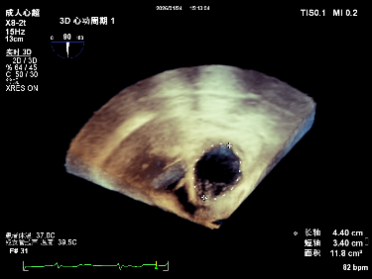

CTA examination revealed an annular area of 23 cm², indicating severe annular dilatation.

Preoperative annulus area: 20.6 cm²

After implantation of two clips, the annulus area is 11.8 cm²